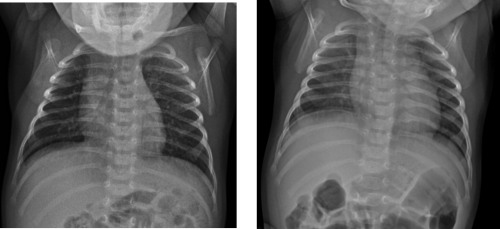

The patient's head CT and all laboratory studies resulted as normal. The initial skeletal survey did not show any radiographic evidence of injury. A follow-up skeletal survey was recommended by the child abuse team.

A FUSS was completed 2 weeks later.

Image 2. AP chest radiograph. A. Normal. B. Follow up, demonstrates healing changes with callus formation from the left second through eighth costovertebral junction

Image 3. Oblique views of left ribs. AP chest radiograph. A. Normal. B. Follow up, demonstrates healing changes with callus formation from the left 2nd through 8th costovertebral junction